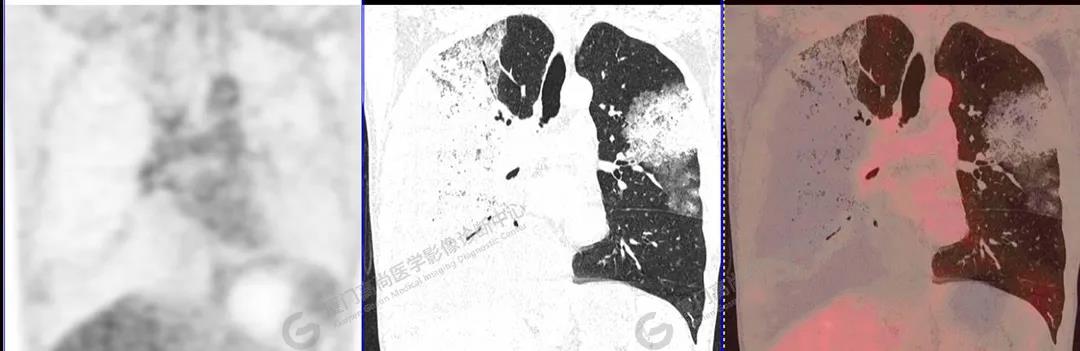

PET/CT影像圖

圖10

PET/CT所見:雙肺大片實(shí)變影及磨玻璃影,部分呈地圖樣改變,累及右肺尖,部分放射性攝取輕微增高,SUVmax 1.77,其內(nèi)見多發(fā)支氣管充氣征象。

影像診斷: 雙肺大片實(shí)變影及磨玻璃影,大部分代謝不高,局部代謝輕微增高,考慮肺泡蛋白沉積癥,建議病理學(xué)檢查或肺泡灌洗物檢查。

影像學(xué)表現(xiàn):HRCT上雙肺斑片影,以肺門為中心呈蝶翼狀對稱分布;病變可隨機(jī)分布在中央?yún)^(qū)、周圍區(qū)或全肺葉,病灶與正常分組織分界清楚,呈典型“地圖樣”改變;有支氣管充氣征,但表現(xiàn)為充氣支氣管細(xì)小且數(shù)量及分布稀少;“碎石路”征由彌漫性磨玻璃影及內(nèi)部網(wǎng)格樣小葉間隔增厚組成(鋪路石樣表現(xiàn))。無空洞、蜂窩狀改變、淋巴結(jié)腫大、胸腔積液及明顯實(shí)變等。肺內(nèi)病灶累及范圍、磨玻璃密度高低與PAP患者的病情嚴(yán)重程度相關(guān),嚴(yán)重者病灶累及全肺,同時出現(xiàn)肺內(nèi)大片實(shí)變,并見充氣支氣管征象。PAP影像學(xué)表現(xiàn)程度與臨床癥狀、體征嚴(yán)重程度不成比例,表現(xiàn)為影像改變重,臨床癥狀輕。